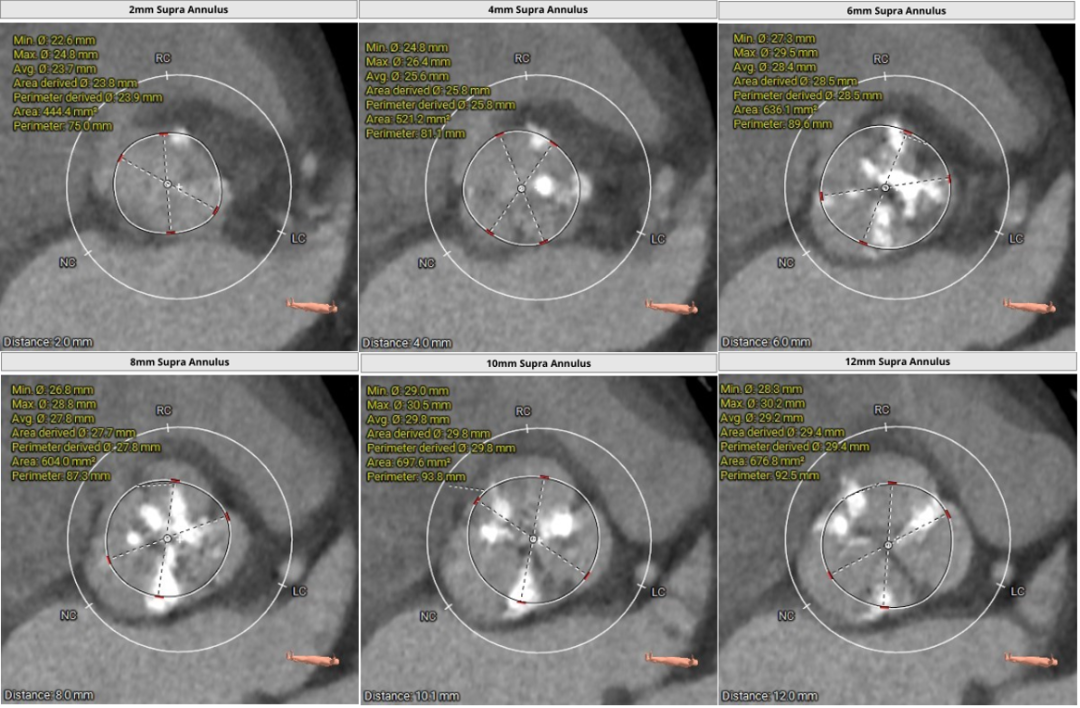

主动脉根部评估:

瓣环上解剖结构评估: